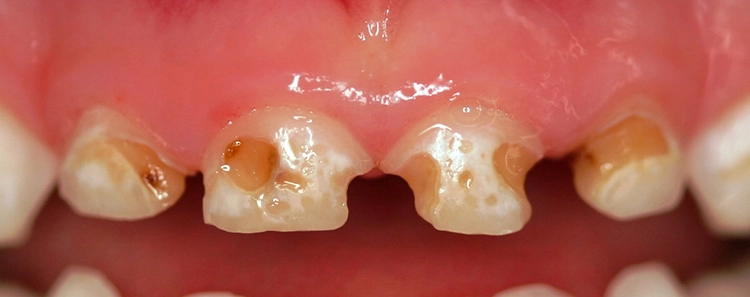

Ein 4-jähriges mäßig kooperatives Kind erscheint zur Kontrolle in der Zahnarztpraxis. Bei der klinischen Untersuchung sind offensichtlich zwei (scheinbar kleinere) approximal kavitierte kariöse Läsionen im Unterkiefer zu sehen sowie Läsionen an den Oberkieferschneidezähnen (Abb. 1a und b). Eine Versorgung dieser Zähne scheint nach klinischer Untersuchung bei diesem Kind noch ambulant möglich.

Erst eine weitergehende röntgenologische Untersuchung zeigt das ganze Ausmaß des Kariesbefalls (Abb. 1c). Das Kind wies an fast allen Milchzähnen bereits Dentinkaries, zum Teil auch schon sehr tiefe Läsionen (Zahn 75), auf. Solch ein Befund scheint bei zahlreichen konventionell-restaurativen Maßnahmen bei altersentsprechender mäßiger Kooperation (fast) nur in Narkose behandelbar.